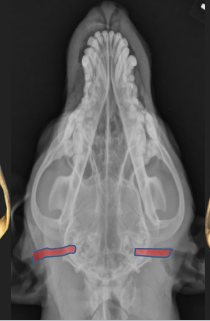

Horizontal Ear Canal